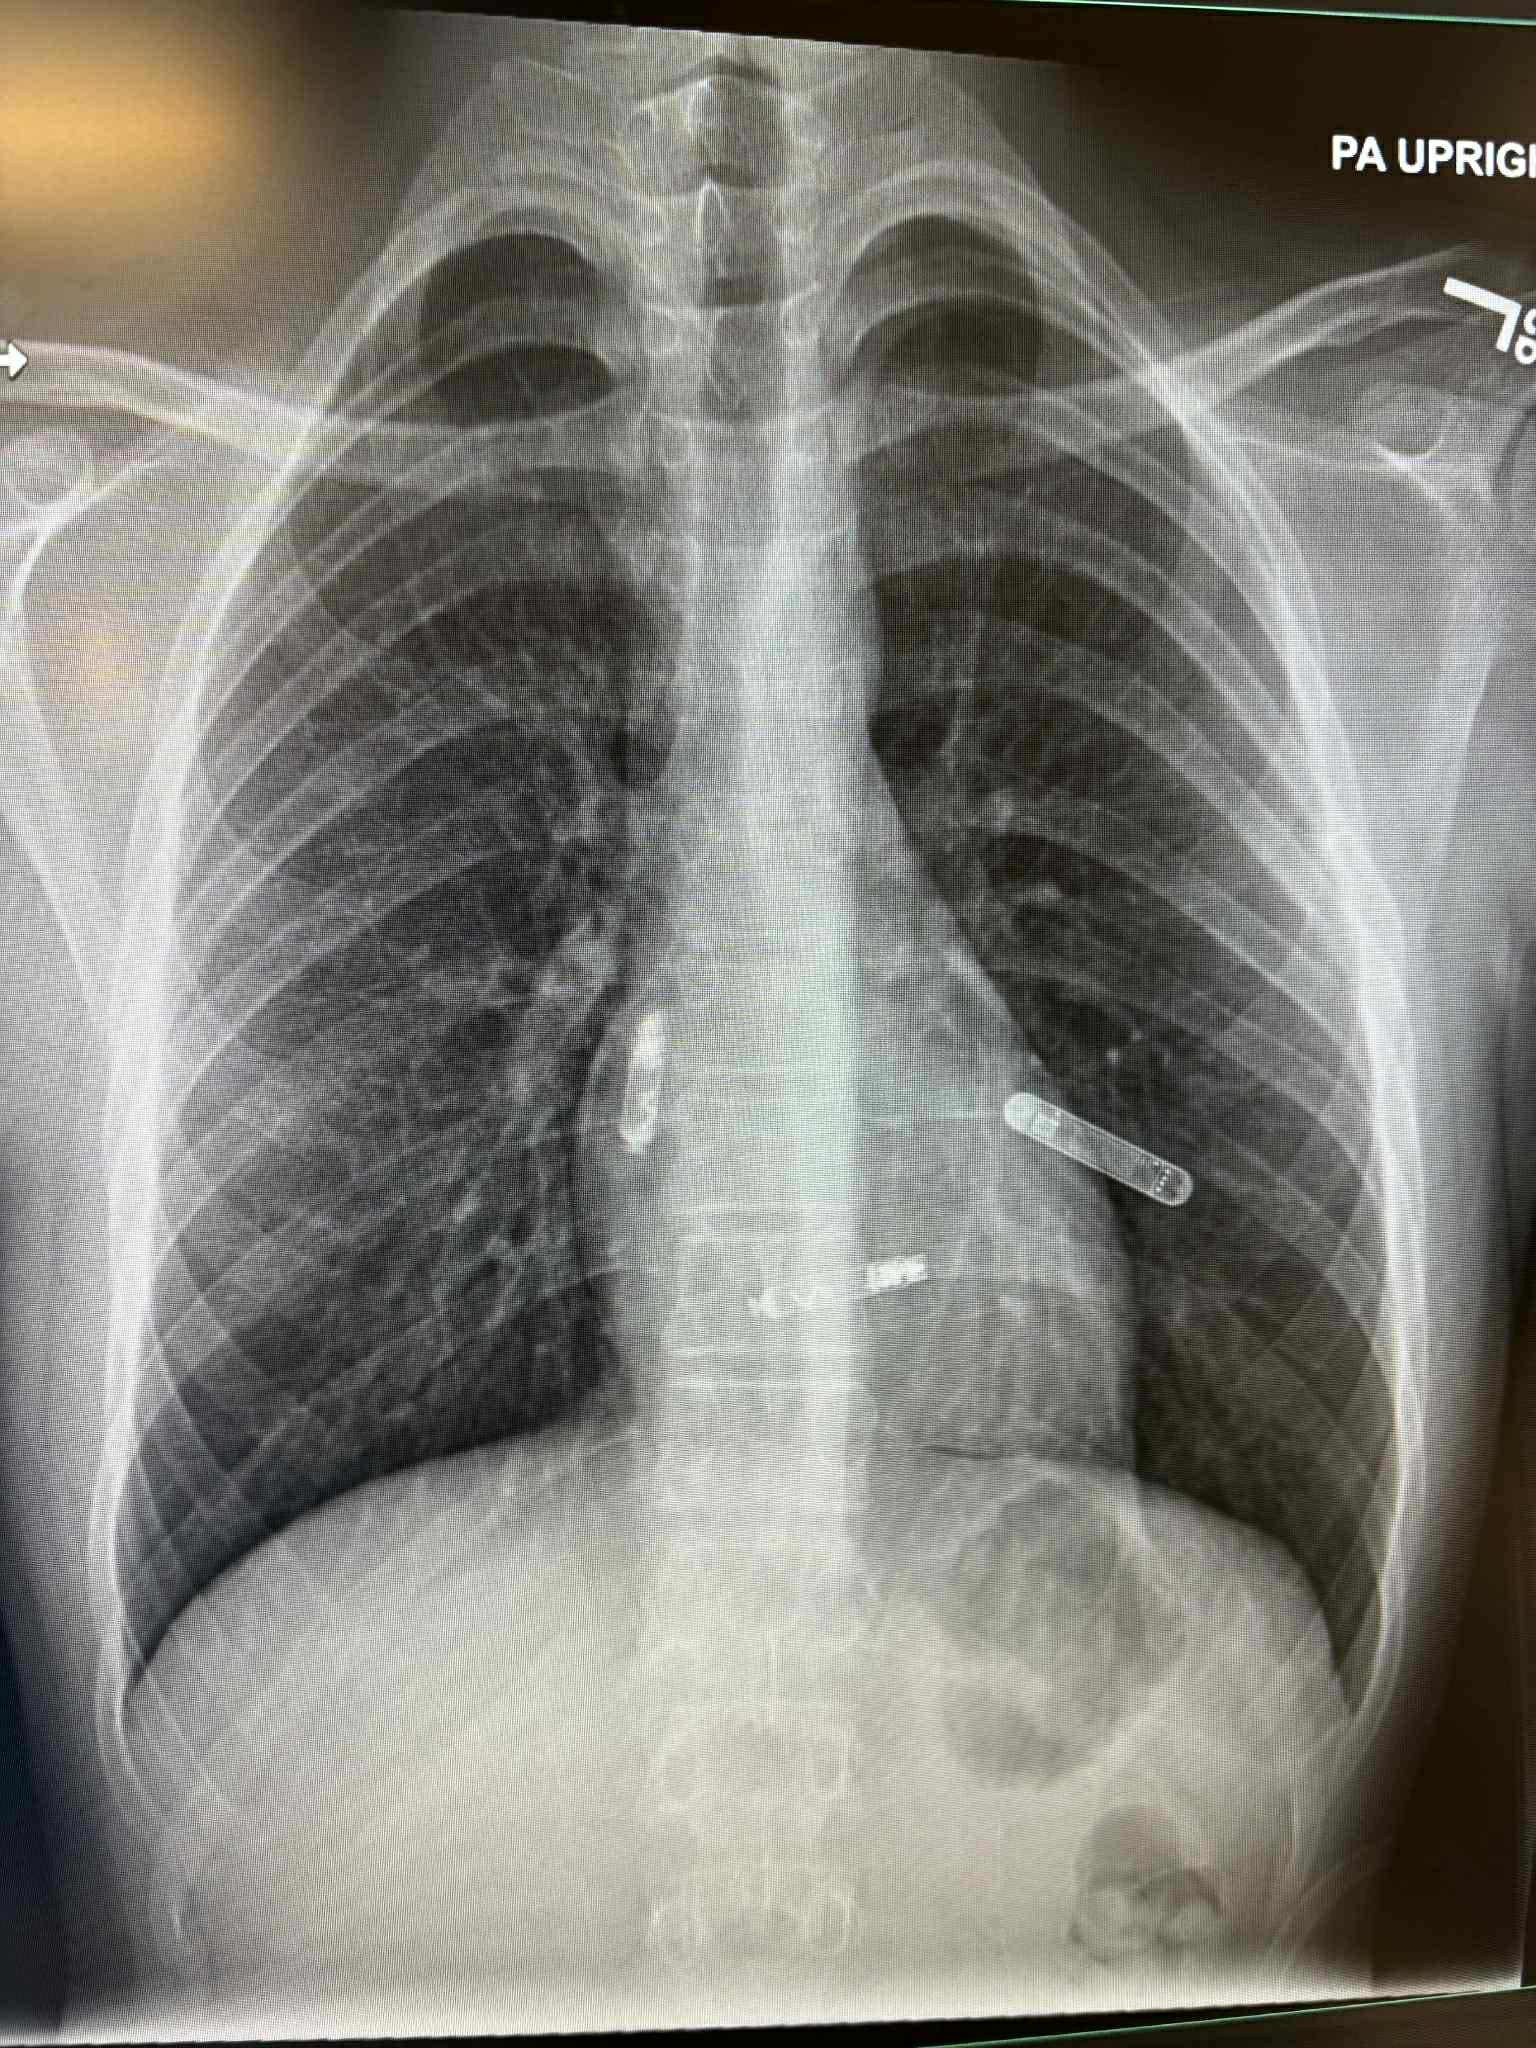

Dr Svjetlana Tišma Dupanović, kardiolog i pedijatar, uspješno je prije nekoliko dana pacijentu ugradila dvokomorni pejsmejker direktno u srčane šupljine – u pretkomoru i komoru – koji sinhronizovano stimulišu pravilan rad srca.

To je, kako je na Facebooku objavio bh naučnik dr Edhem Čustović, prva takva operacija izvedena na Floridi, a ujedno predstavlja veliki napredak u liječenju bolesti srca, posebno za pacijente sa poremećajima srčanog ritma i slabijom pumpnom funkcijom srca.

“Tradicionalni pejsmejkeri postavljaju se ispod kože grudnog koša, a žice prolaze kroz vene do srca. Nova tehnologija, koju je primijenila dr Tišma-Dupanović, omogućava direktnu ugradnju uređaja unutar srca — bez žica koje prolaze kroz krvne sudove. Ovaj dvokomorni (biventričularni) pejsmejker sinhronizuje rad pretkomora i komora, čime se postiže pravilniji ritam i veća efikasnost pumpanja krvi”, napisao je Čustović.

Foto: Dr Svjetlana Tišma Dupanović (Facebook/Dr Edhem Čustović)